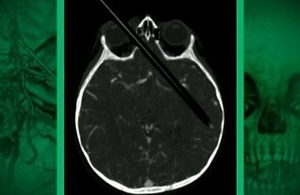

Он обратился за помощью в одну из клиник города Ахен. После томографии, немецкие врачи увидели, что в голове мужчины застрял 10-сантиметровый карандаш. Он прошел сквозь глазницу и уперся в его глотку.

После удаления карандаша, боли в голове утихли, а зрение стало восстанавливаться. Карандаш пережал глазной нерв. Сам пациент не знает, откуда в его голове посторонний предмет. Однако он высказал подозрение, что карандаш мог попасть в его голову еще в детстве, когда он случайно упал.